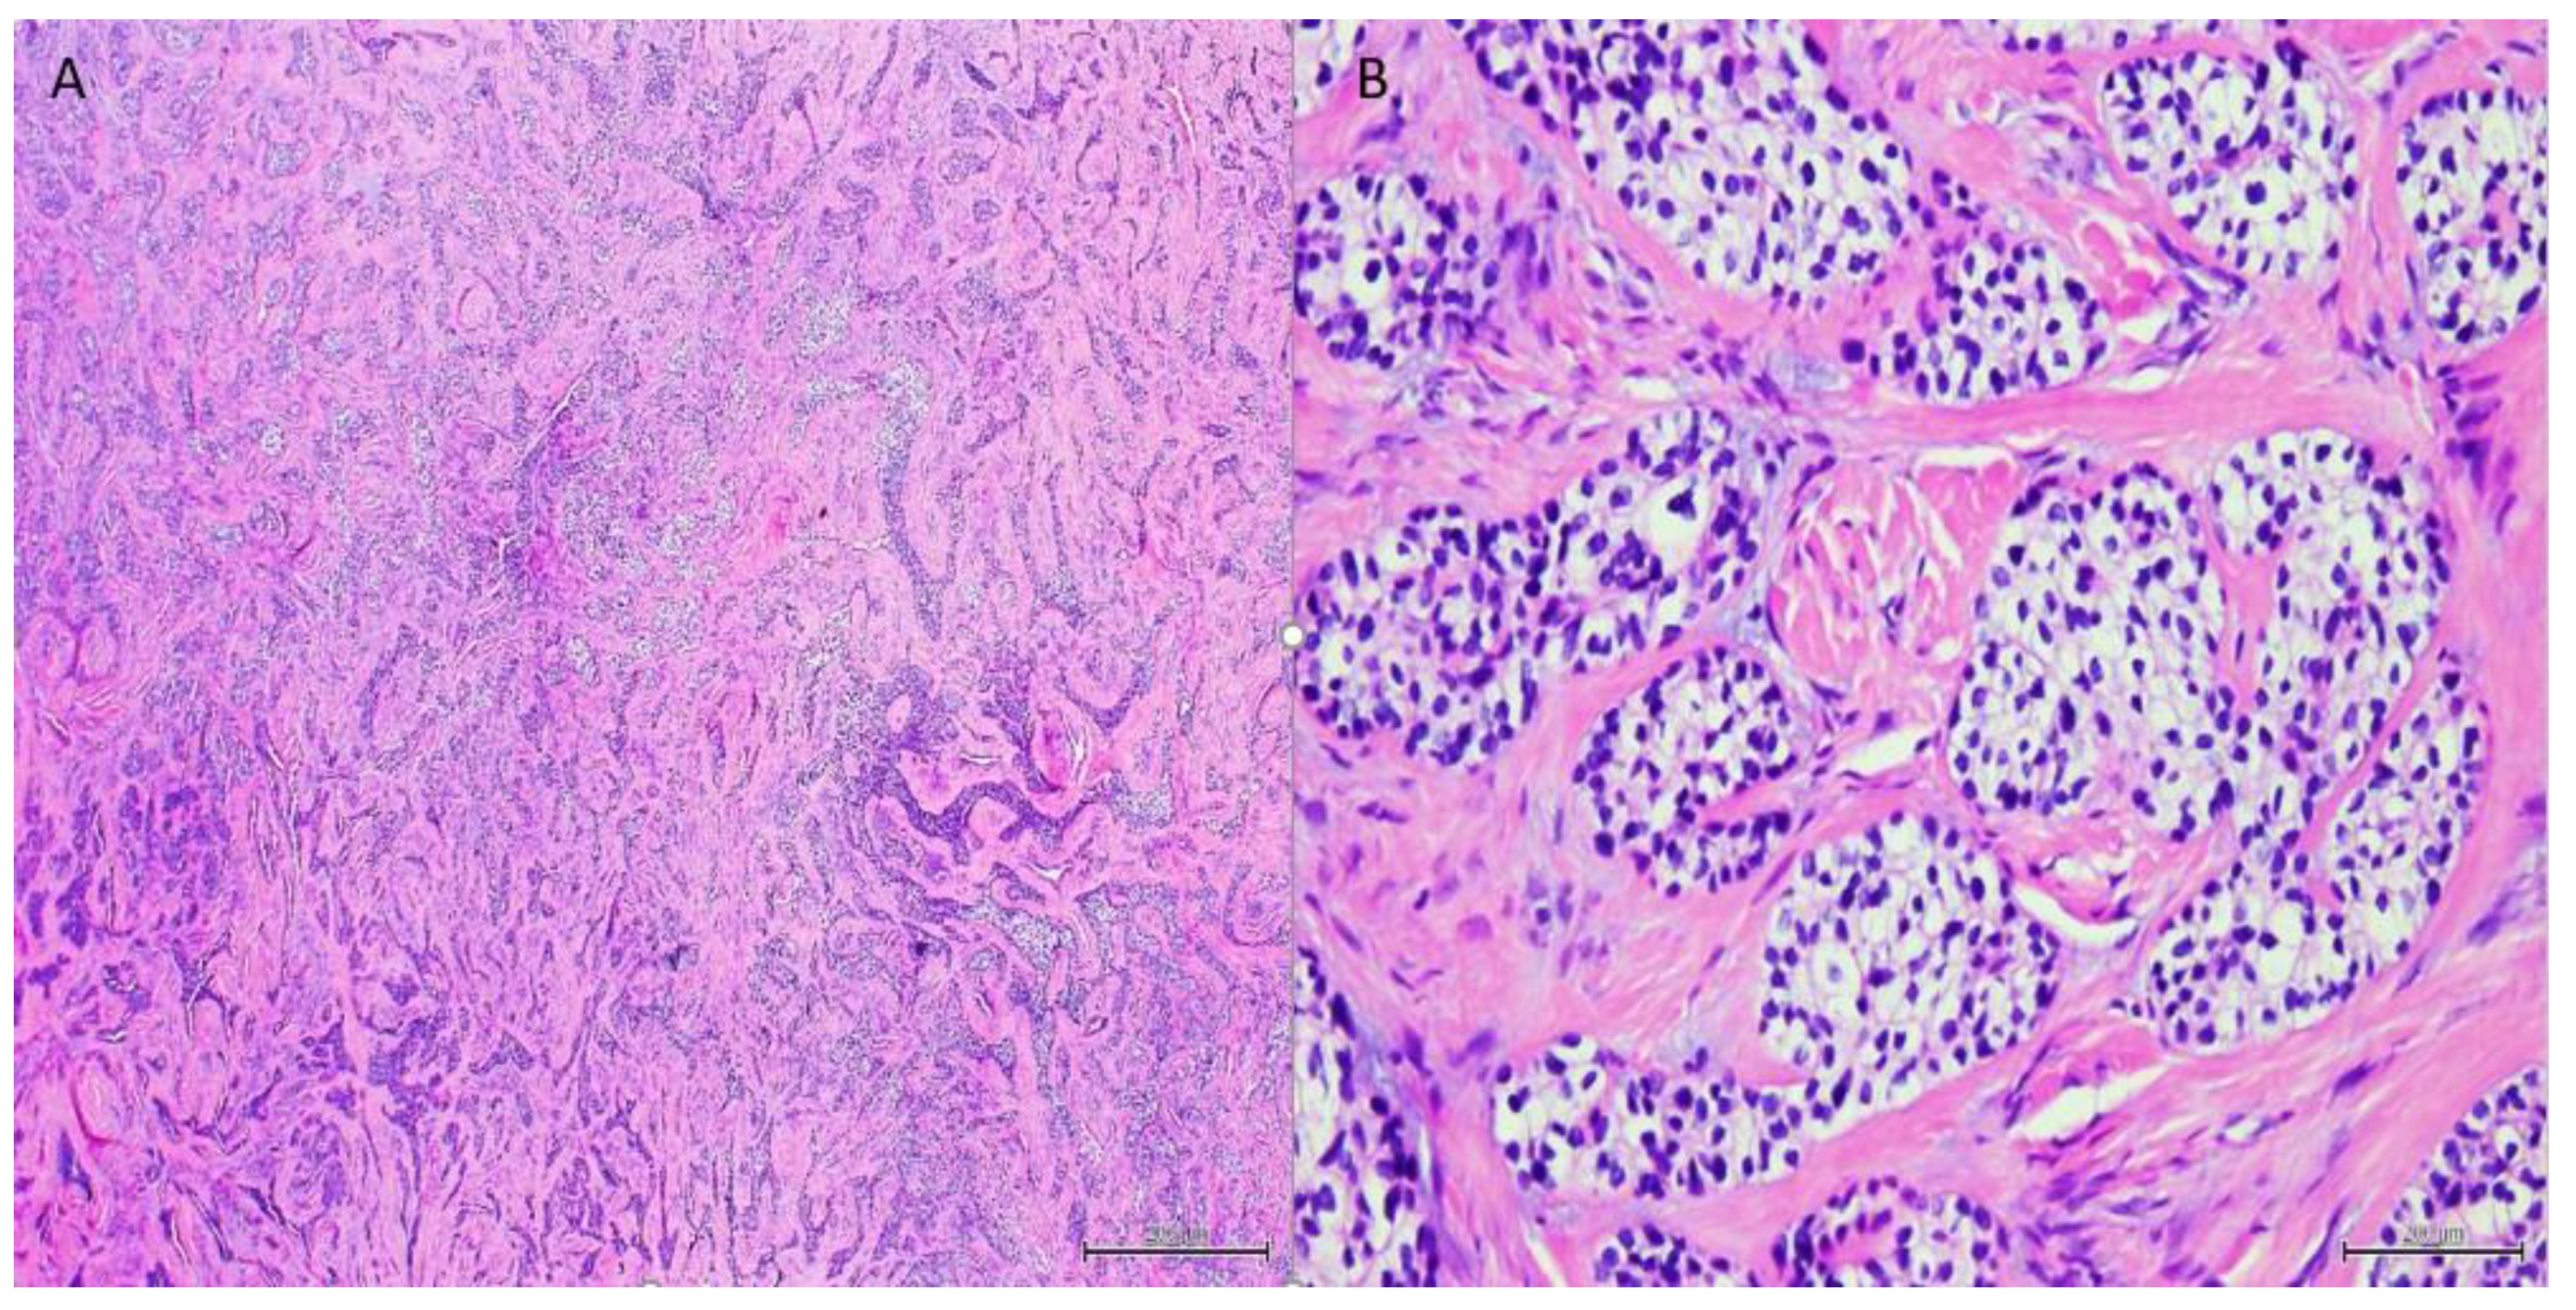

| Staining/IHC | PAS (+) D-labile Mucicarmine (−), p63 (+) CK5/6 (+), CK19 (+) | PAS (+) D-labile Mucicarmine (−) CK5/6 (+) | H&E only |

| Morphology | Infiltrative, non-encapsulated malignant neoplastic odontogenic epithelial proliferation with clear cell component in a dense fibrous connective tissue stroma. Neoplastic cells arranged in anastomosing trabeculae. Nuclear hyperchromasia and pleomorphism surrounded by clear, vacuolated cytoplasm. Stroma was hyalinized, densely collagenized, hypocellular, and hypovascular. | Neoplastic odontogenic epithelial proliferation diffusely infiltrated the connective tissue stroma. Neoplastic cells arranged in islands of variable size, trabeculae, and nests. Nuclei were hyperchromatic, central, and pleomorphic surrounded by clear cytoplasm. | Infiltrative odontogenic epithelial neoplasm intermixed with eosinophilic dentinoid matrix. Neoplastic cells arranged in infiltrative, non-encapsulated sheets, cords, and nests of polygonal cells with central hyperchromatic and slightly pleomorphic nuclei surrounded by clear cytoplasm and occasional pale eosinophilic cytoplasm. Occasional mitotic figures were noted. Neoplastic epithelial sheets and cords blended with eosinophilic cellular matrix without cellular rimming consistent with dentinoid deposits. |